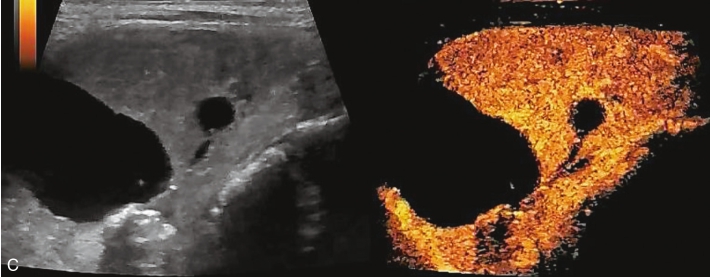

注入造影剂后甲状腺左叶囊实性结节内始终呈无增强,边界清晰,结节周围甲状腺被膜完整,见图1-3-4、ER1-3-2。

(1)周围囊壁呈均匀高增强,边界清,内部始终无造影剂灌注。

(2)结节周边被膜连续且完整。

图1-3-4 甲状腺囊肿伴出血超声造影图

A.注入造影剂后17s图像;B.注入造影剂后28s图像,结节内部始终呈无增强